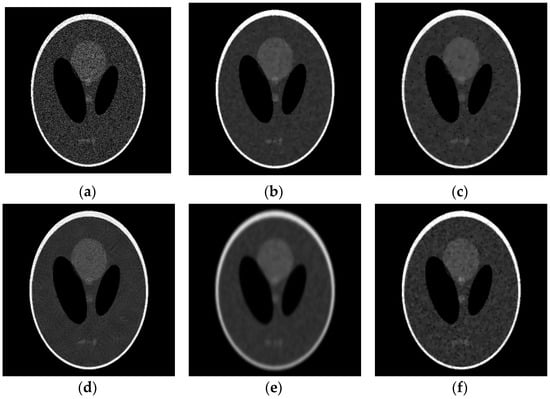

5.1. Synthetic Image Experiments

5.2. Real Ultrasound Image Denoising Experiment